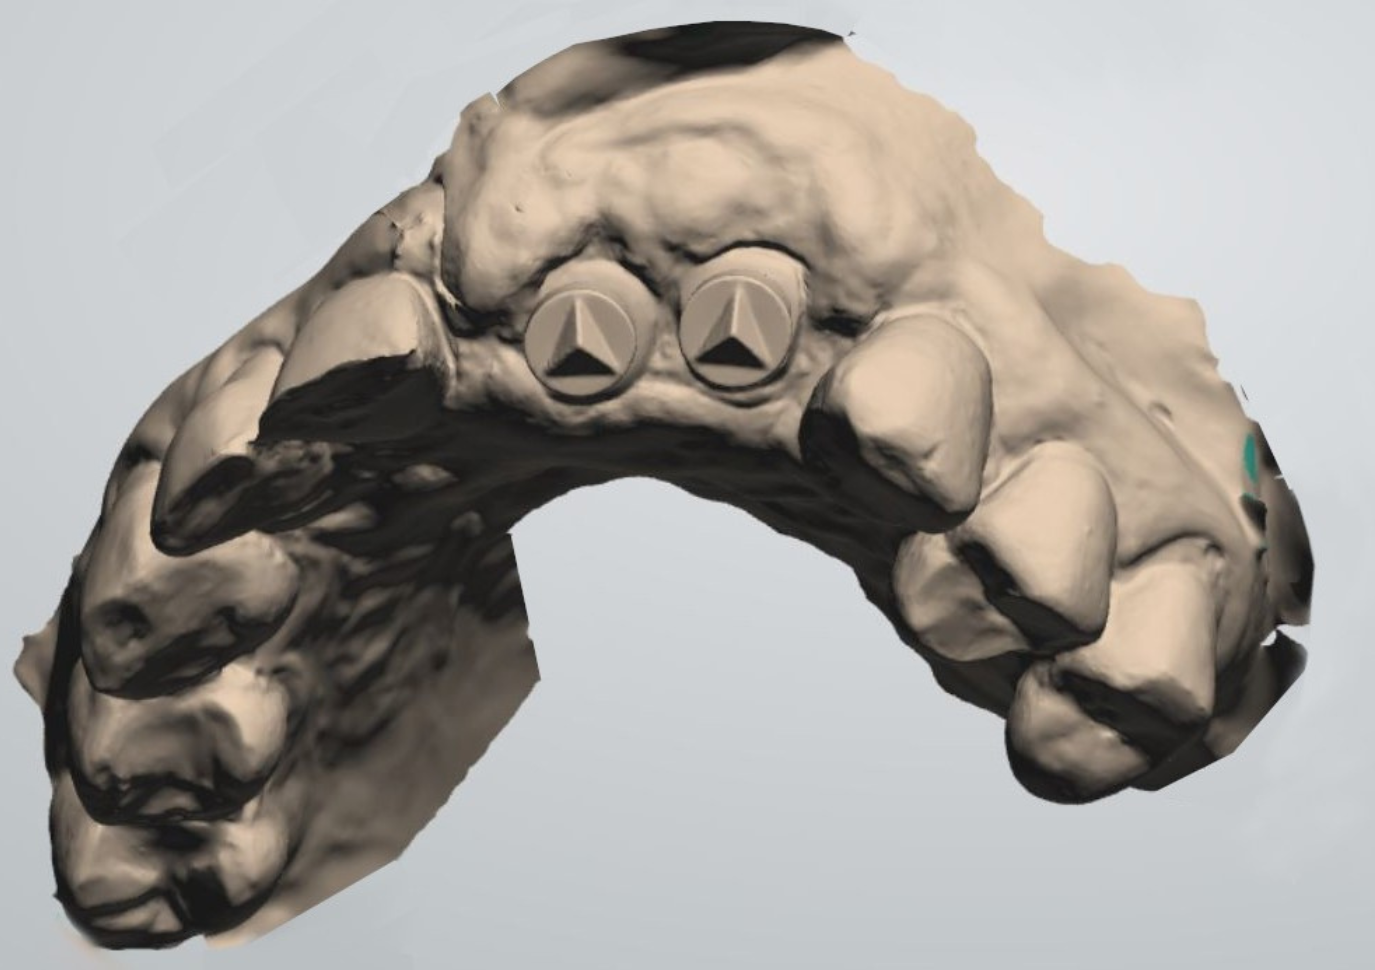

Figure 2.

At time of suture removal, the ScanPegs were seated inside the Esthetic Healing Abutments, and an intraoral scan was taken without the need to remove the abutments. The advantages are that soft tissue is left to heal undisturbed and dislocation of graft material is avoided.